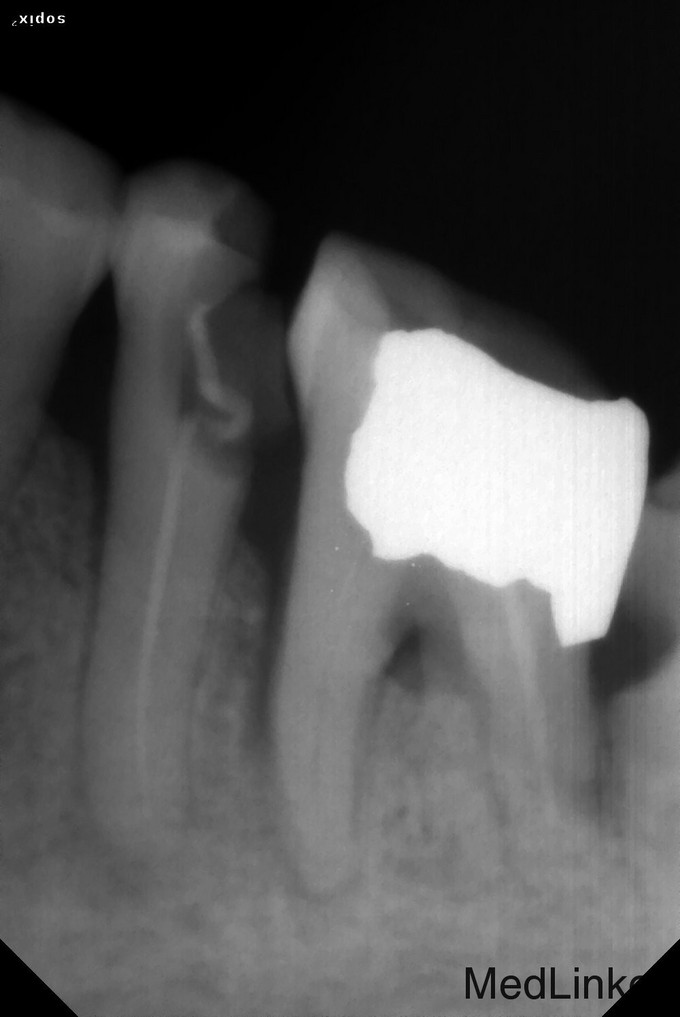

一年后复查:患牙正常使用,无明显异常。检查:充填物在,叩诊叩痛(-),X线片示:根尖周骨小梁致密。 讨论: 1、现代根管治疗学认为根管开放引流是根管治疗后疾病的一大病因,我个人也主张:不做没必要的开放。但是,不等于严禁根管开放。 2、本世纪初以前有学者认为,开放减轻了疼痛是因为通过氧气消灭根管内的“厌氧菌”,我个人认为:开放是为了脓腔引流。 3、开放的一个不可忽视的问题是,口腔内细菌的逆向根管内定植,同时根尖孔(相对于引流通路)过于狭小经常被脓栓阻塞,以及下牙没有重力引流的可能。口腔含漱液的使用可以暂时减少口腔内的细菌,以及局部吮吸,可以有效减小开放的副作用——局部吮吸,灵感来自于“负压引流”。 4、开放引流的时间根据病人以及患牙的具体情况而定,经验(血淋淋的教训)是随年龄增大而增多,最多多少天?还是应该以患者、患牙的状态为主要标准点,毕竟,开放是为了引流。我目前通常参考的时间控制是:年轻人1天,老人2天,此病例3天又是因为屈从于患者的就诊时间。故此复诊时加大了冲洗的程度。 5、此病例约诊间疼痛的病因首先考虑氢氧化钙的封药时机。氢氧化钙毕竟也有刺激性,激惹了根尖周组织。 6、氢氧化钙在根尖周炎中的作用有抗菌和诱导活化成骨细胞,而纳米羟基磷灰石可以直接提供成骨原料,碘仿及甲硝唑可以抗菌。 7、将塑化当作根管糊剂使用,并冷测压,目前一年后复查的病例较少,样本小,有待于进一步研究。